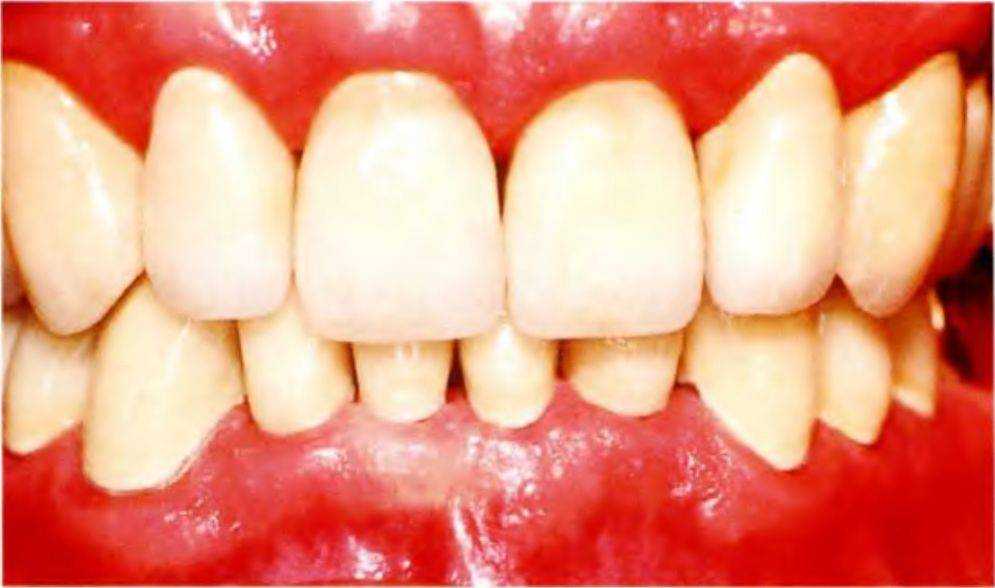

При отсутствии патологии ВНЧС или жевательной мускулатуры можно проверить возможность адаптации пациента к новому межальвеолярному расстоянию с помощью капп или провизорных реставраций. В данном случае после увеличения межальвеолярного расстояния контрольный период составил шесть месяцев, в течение которых у пациента не возникло дискомфорта. После этого изготовили окончательные коронки с учетом новых параметров (рис. 6-5i и 6-5j).